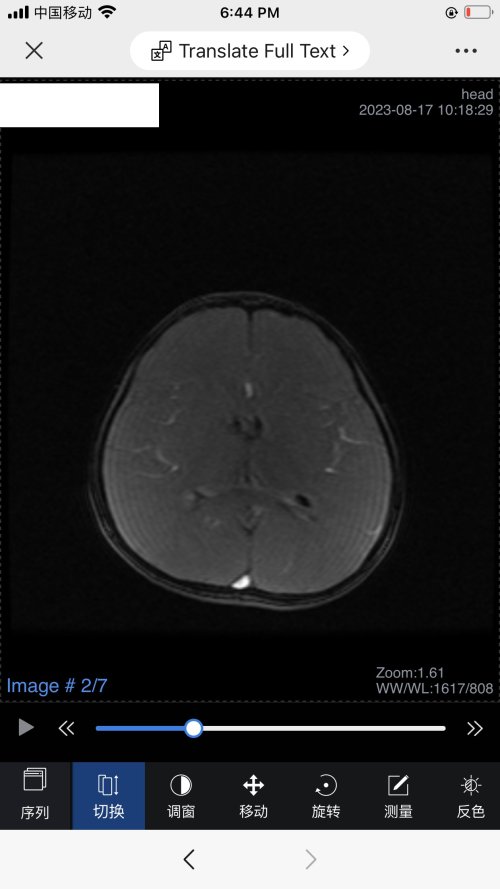

反馈下情况,孩子在国内的医院已经进行过一轮全面检测,没发现什么问题,但是现象是存在的。医生也没什么办法。医生说核磁共振和脑电图没问题,我们也不是很看得懂,各位如果懂的,请指点一下。另外进行了部分基因检测,没发现异常。下一步,我们国庆后打算去更权威的医院去碰碰运气。谢谢各位!

513.6 KB 查看: 103

532.8 KB 查看: 142

551 KB 查看: 132

526.8 KB 查看: 133

510 KB 查看: 103

506.4 KB 查看: 124

495.7 KB 查看: 165